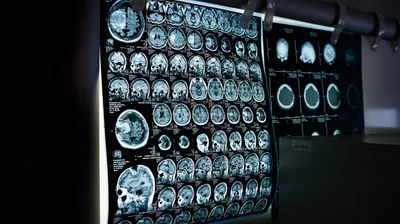

Ученые заявили, что у людей с ярко выраженными психопатическими чертами изменена структура четырех областей мозга, связанных с контролем импульсов, эмоциональной регуляцией и социальным поведением, сообщает Zakon.kz.

"Нейровизуализацию мозга провели у 39 мужчин, набравших высокие баллы по шкале психопатии PCL-R. Этот инструмент позволяет оценить два основных компонента психопатии: эмоциональную отчужденность (Фактор 1) и антисоциальное поведение (Фактор 2)", – говорится в исследовании.

После МРТ-сканирования участников полученные данные были проанализированы с помощью Julich-Brain Atlas – цифровой карты мозга, позволяющей сопоставлять анатомические особенности с поведенческими характеристиками.

Наиболее выраженные отличия обнаружили у тех, кто набрал высокие баллы по Фактору 2. У них оказался снижен объем четырех участков мозга – базальных ганглий, таламуса островковой коры, передней поясной извилины и правой части гиппокампа. Эти области играют важную роль в регуляции эмоций, мотивации, обучении и социальном взаимодействии.

"Также в среднем общий объем мозга у людей с выраженной психопатией был на 1,45% меньше, чем в контрольной группе", – пояснили ученые.

При этом для Фактора 1 – эмоциональной отстраненности – достоверных различий в структуре мозга выявлено не было. Это, по мнению исследователей, может свидетельствовать о том, что нейробиологическая основа различных аспектов психопатии неоднородна.